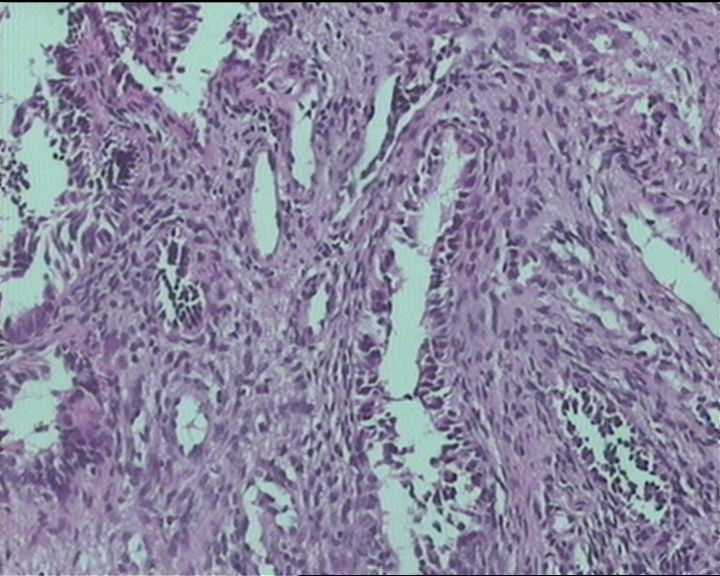

54岁女性,临床“宫颈息肉”送检;巨检:组织一块1。5*1CM,灰红。

Sternberg病理学上诊断宫颈原位腺癌的标准是腺体的上皮去粘液分化,呈乳头状或筛网状增生,核分裂易见,这例显然达不到此标准。此例还是归入到腺上皮不典型增生为好。

It is benign. Benign endocervical polyp with tubal metaplasia.

输卵管粘膜化生

细胞及腺体均有异形,图6、11、16象有纤维间质反应,考虑高级别上皮内瘤变/原位癌,腺癌不能除外。